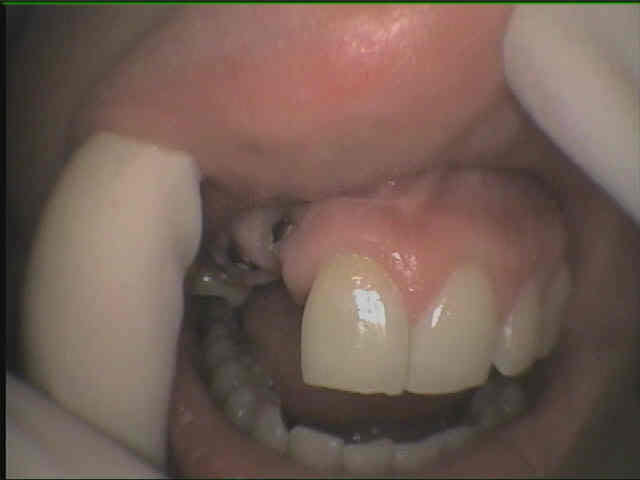

Le praticien qui a posé me dit que c'est un biotech : je ne trouve pas que la radio ressemble à la game biotech ... une explication ?

et encore ca ce n'est rien : look le superbe positionnement !!! c'est un sto qui a fait ca . Je ne sais pas encore si je fais ou pas

oulà....si tu veux un conseil....touche à rien...retour à l'envoyeur!!!

amha c'est le genre de cas qui va te pourrir la vie...

chance d'avoir une esthétique acceptable....zéro...et c'est toi qui va essuyer les doléances "Dr, votre prothèse elle est pas jolie..."...bein oui, vu le positionnement des implants...on peut pas faire de miracle...

Même conseil que Pluton : surtout ne rien faire. Tout ce que tu feras la-dessus ne sera que du bricolage.

Je suis d'accord avec vous mais je connais le père qui me l'envoie ... je l'ai deja prevenue de la nullité du traitement mais heureusement elle a un sourire qui ne découvre pas .ca m'embete de la laisser dans la panade, je pensais faire des provisoire pour qu'elle puisse se rendre compte et si cela ne va pas je la renvoie au poseur

Si vraiment j'étais obligé de faire quelque chose (ma famille saucissonnée à la maison toussa...) je tenterai une petite prothèse trans-vissée avec fausse gencive. Ça serait mieux qu'un trou mais difficile à entretenir.